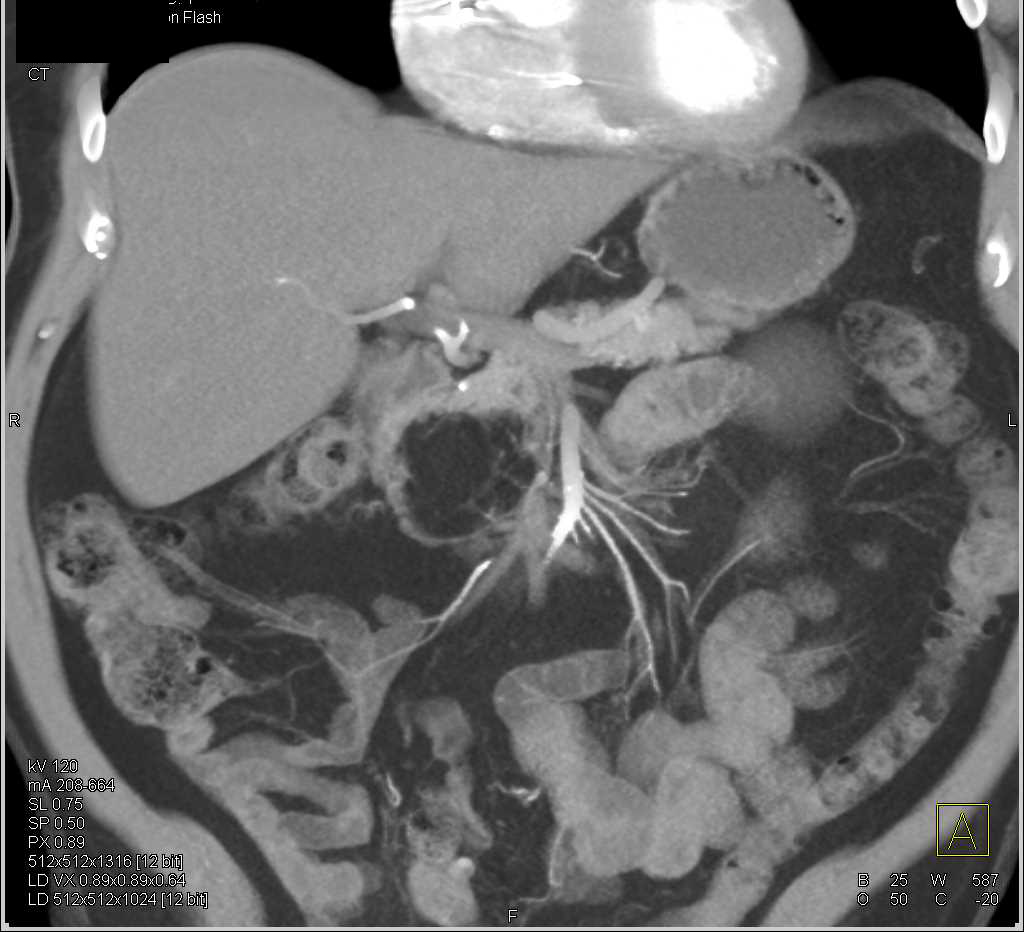

Hemoperitoneum S/P Whipple Procedure